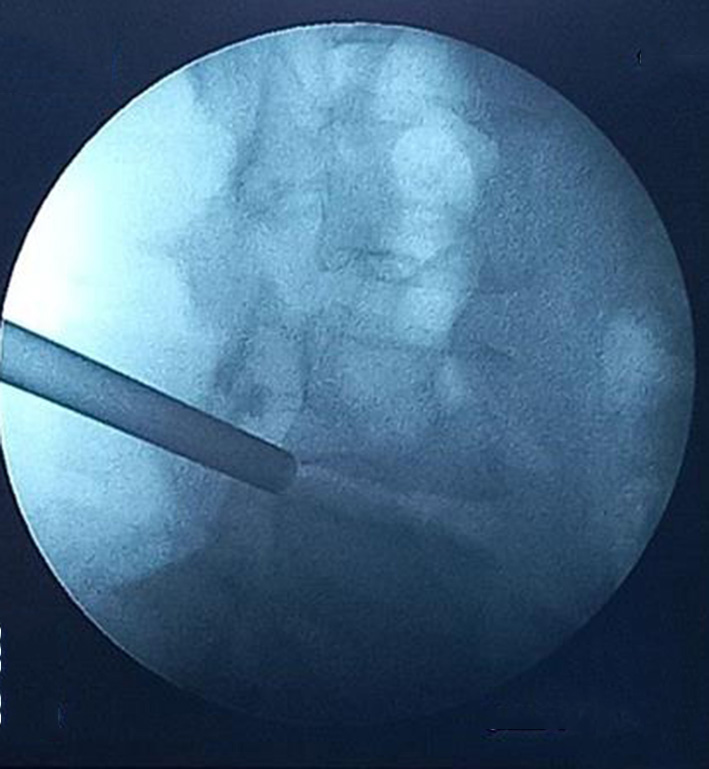

A transforaminal endoscopic microdiscectomy of the L4-L5 intervertebral disc on the right was performed. Fig. 7 shows fluoroscopic guidance of the endoscope port placement in the specified area of the L4-L5 intervertebral space on the right.

A

B

Fig. 7. Port placement: A – lateral projection; B – straight projection